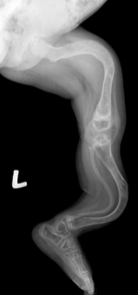

Rad - Achondroplasia

fetal US can show shortened limbs and enlarged head

genetic test can confirm diagnosis

long bones appear short and thick with a wide metaphysis

long fibula

bowing legs